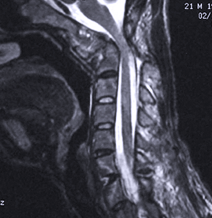

The region where the head and neck articulate has unique and highly complex anatomy and function in a high-risk region that typically requires particular expertise in the treatment. The treatment largely depends upon a clear understanding of the biomechanics of this region, and the surgical treatment often requires precision surgical techniques in a region that is infrequently treated by neurosurgeons and orthopedic spine surgeons.

Dr Johnson has extensive experience having performed over 500 procedures that include transoral surgery, treating C1-2 degenerative and deformity cases, tumors, and fractures involving the odontoid and atlanto-axial complex.